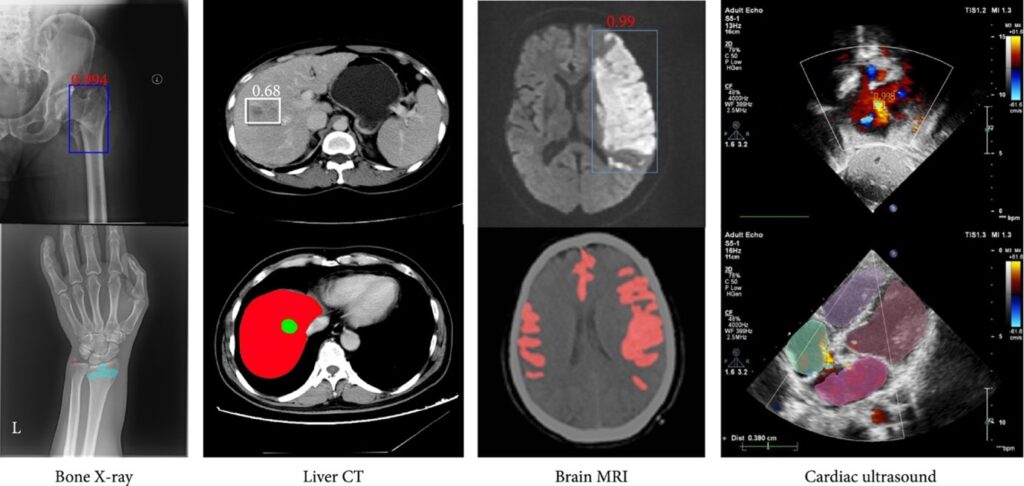

Y no solo eso: en hospitales, ayuda a detectar enfermedades en rayos X, y en bancos, atrapa fraudes antes de que te des cuenta. Es como un superpoder silencioso que está cambiando el mundo.